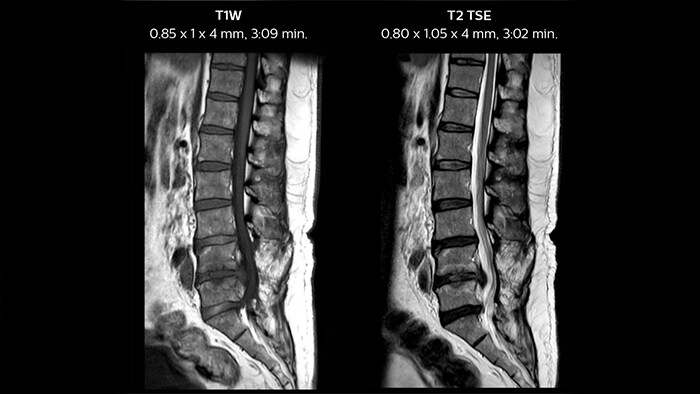

In this patient MRI images show spondylotic degenerative changes in the lumbar spine, in view of the osteophyte, disc desiccations and Sc hmorl’s nodes with lumbarization of S1, post-laminectomy changes at L5-S1 and S1-S2 levels with disc protrusion and extrusion, and diffuse disc bulges from L3-L5 with nerve root compression.